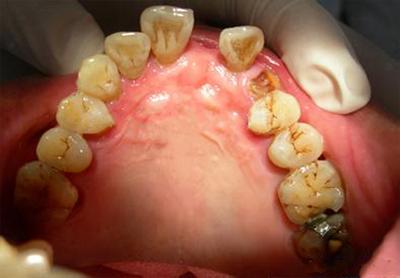

1.对咬牙向缺牙区生长

对咬牙向缺牙区生长后,为了有足够空间制作假牙,会视缺损的量将对咬牙修短,或是利用矫正将牙齿推原有的位置,会让治疗变得更复杂。